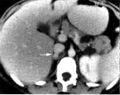

يمكن أن يساعد التصوير المقطعي المُحَوْسب أو التصوير بالرنين المغناطيسي T2 على الرأس والرقبة، والصدر، والبطن في تحديد مكان الورم. ويمكن أيضًا تحديد المكان عن طريق المسح الضوئي MIBG، باستخدام metaiodobenzylguanidine . أما التحديد الأدق فيمكن الحصول عليه في بعض مراكز المسح باستخدام PET-CT أو PET-MRI مع 18F] fluorodopamine] أو FDOPA.[10]